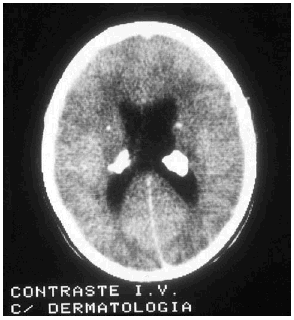

Las manifestaciones tumorales son hamartomas tuberosos múltiples, bien delimitados, con potencial blastomatoso, benigno o maligno que se encuentran a nivel de corteza cerebral y más raramente en cerebelo o en médula espinal. Su transformación maligna puede conducir a astrocitomas de células gigantes y glioblastomas con sintomatología de expansión intracraneal: hipertensión, cefaleas, vómitos, alteraciones visuales y papiledema. El electroencefalograma (EEG) está alterado en el 80% de los pacientes, pero las anomalías encontradas no son específicas de la enfermedad. El líquido cefalorraquídeo (LCR) es normal o, como mucho, puede presentar una ligera elevación de las proteínas. En los estudios radiológicos simples se pueden observar calcificaciones de los ganglios de la base o paraventriculares (fig. 7) y en la TAC o en la RMN cerebral tubérculos corticales, nódulos subependimarios, lesiones en la materia blanca periventricular profunda, etc.

FIG. 7.--Calcificaciones paraventriculares (tercer ventrículo).

-- TAC y RMN craneal 27. Son imprescindibles para evaluar disfunción neurológica y la presencia simultánea de astrocitoma glial subependima-rio, muchas veces presente en el momento del diagnótico inicial. Deberá ser reevaluado cada 1-3 años.